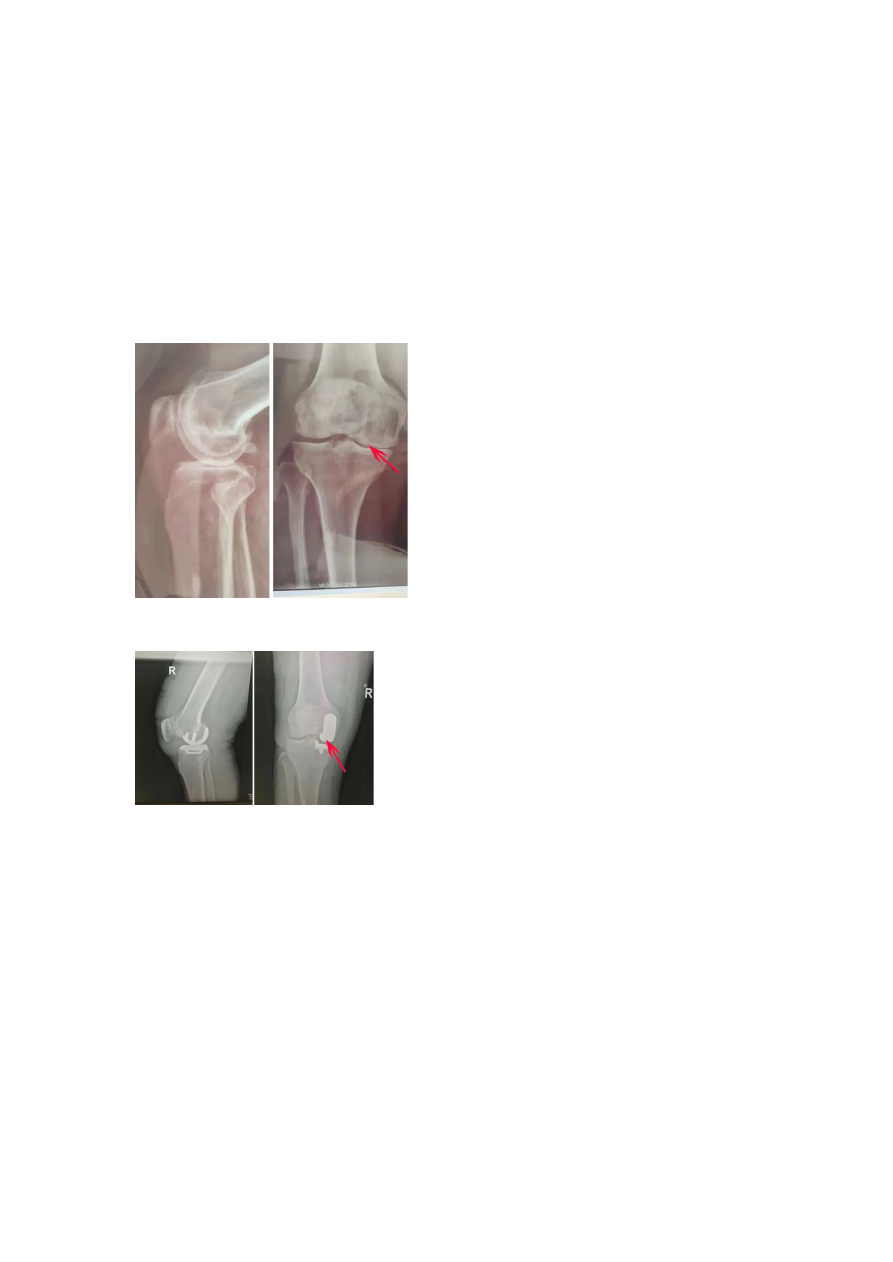

王先⽣术前

X

线,正位可⻅内侧间室⻣对⻣,侧位可⻅平台前内侧⻣磨损

王先⽣接受单髁置换⼿术后的

线,磨损的内侧间室已经完全被修补替代